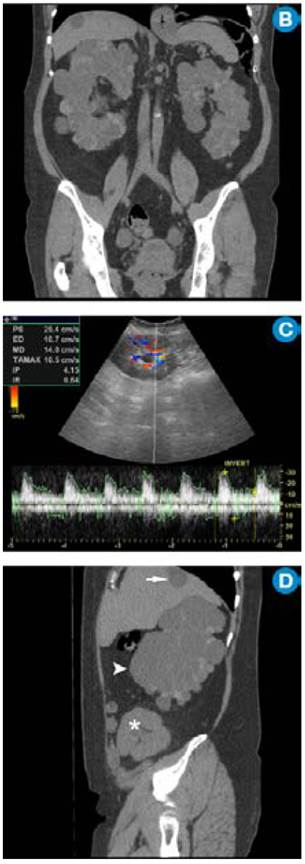

Enfermedad renal poliquística dominante en paciente trasplantado. A) MR coronal T2. Se observan los ríñones aumentados de tamaño con múltiples quistes con diferentes intensidades de señal por contenido hemático en diferentes fases. B) MR axial T1 fatsat con contraste: el aumento de la intensidad de señal de los quistes es secundario al contenido hemático. C) MR coronal T1 fatsat simple (arriba) y contrastado (abajo): se nota la ausencia de realce de las lesiones quísticas que confirma el hallazgo. Continúa.

Figura 2: Enfermedad renal poliquística dominante en paciente trasplantado. A) MR coronal T2. Se observan los ríñones aumentados de tamaño con múltiples quistes con diferentes intensidades de señal por contenido hemático en diferentes fases. B) MR axial T1 fatsat con contraste: el aumento de la intensidad de señal de los quistes es secundario al contenido hemático. C) MR coronal T1 fatsat simple (arriba) y contrastado (abajo): se nota la ausencia de realce de las lesiones quísticas que confirma el hallazgo. Continúa.

D) MR coronal T2: se observa el riñón trasplantado (asterisco).

Figura 2: D) MR coronal T2: se observa el riñón trasplantado (asterisco).

Fuente. Archivo personal JM.

Por su alta sensibilidad, disponibilidad y bajo costo, la ecografía renal es el estudio inicial con el que se pueden observar riñones grandes con quistes bilaterales, múltiples y tamaño variable (figura 1); sin embargo, es altamente dependiente del operador y es menos sensible para detectar quistes <1cm que se visualizan mejor en la escanografía o en la resonancia magnética 24. Pese a que en la actualidad no existen criterios estandarizados en estas dos técnicas imagenológicas para el diagnóstico de la PKD, la tomografía computarizada (TC) y la resonancia magnética (RM) son más sensibles para el diagnóstico de los quistes en los casos dudosos, la detección de complicaciones, la valoración de la progresión y la respuesta al tratamiento 25 (figura 2).

En la ARPKD, el diagnóstico puede ser realizado en el período intrauterino, neonatal o en los primeros meses de vida por medio de una ecografía renal en la que se observan los riñones aumentados de tamaño, con pérdida de la relación corticomedular, hipoplasia pulmonar y oligohidramnios debido al bajo gasto urinario 31. En edades posteriores se prefieren las imágenes por TC y RM para seguimiento o, como ya se mencionó, para casos dudosos. En las fases tempranas, los riñones pueden ser de tamaño y forma normal; en las fases posteriores aumenta el número y el tamaño de los quistes, con distribución difusa del parénquima, aumento del tamaño (se alcanzan longitudes de hasta 40cm) y, por consiguiente, aumento del volumen renal. La RM es la técnica de elección empleada para la volumetría de los quistes y del parénquima como indicadores de progresión o de respuesta al tratamiento.